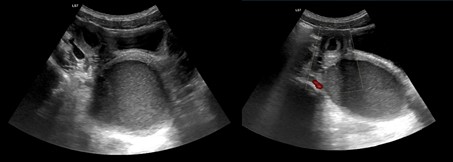

A 12-year-old girl, with an irrelevant medical history, was admitted to the pediatric emergency department with pollakiuria and abdominal and genital pain for two weeks, with worsening in the day before admission. There was a reference to menarche in the six months before, with scarce catamenia and intense dysmenorrhea refractory to NSAIDs. Last catamenia had been two weeks prior to the admission. On physical examination, the lower abdominal quadrants were rigid and painful on palpation and decompression, mainly in the right iliac fossa. An analytical study, urinalysis and pregnancy test were performed, all negative. Therefore, she did an abdominal ultrasound which suggested an hematocolpus (Fig. 1), but could not correctly evaluate the uterus. To better characterization, an abdominal and pelvic computized tomography was carried out which revealed the absence of the right kidney and retroaortic left renal vein, duplication of the uterus, cervix, and vagina, and marked distension of the right hemivagina and endometrial cavity, with hematocolpos, suggesting vaginal obstruction (Fig. 2). Afterwards, she did a renal scintigraphy for a renal morphofunctional assessment, which confirmed a right renal agenesis (Fig. 3). These findings allowed the diagnosis of an OHVIRA syndrome.

Figure 1: Abdominal ultrassound: hematocolpos.